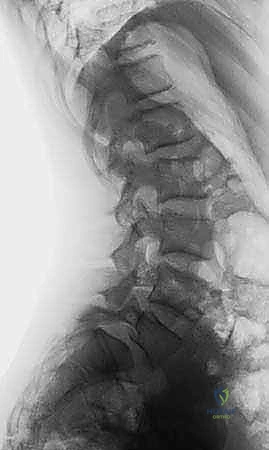

تبدأ رحلة الشفاء في عيادة الدكتور هطيف بتشخيص دقيق وشامل. الانزلاق عالي الدرجة يتطلب تصويراً متقدماً لتحديد زاوية الانزلاق، مقدار الضغط العصبي، وجودة العظام.

- الأشعة السينية الديناميكية (Dynamic X-rays): صور في وضعية الانحناء للأمام والخلف لتقييم مدى عدم استقرار الفقرات وحركتها غير الطبيعية.

- التصوير المقطعي المحوسب (CT Scan): يقدم تفاصيل دقيقة للبنية العظمية، وهو ضروري جداً للتخطيط الجراحي وتحديد مسار المسامير (Pedicle Screws) في الجراحة.

في المنطقة القطنية السفلية، وتحديداً بين الفقرة القطنية الخامسة والفقرة العجزية الأولى (L5-S1)، يقع العبء الأكبر من وزن الجسم والضغط الميكانيكي. يتم الحفاظ على ثبات هذه الفقرات بواسطة مفصلات خلفية (Facet Joints) وجزء عظمي دقيق يُعرف بـ "برزخ القوس الفقري" (Pars Interarticularis). عندما يحدث كسر أو ضعف أو استطالة في هذا البرزخ، تفقد الفقرة دعامتها الخلفية، ومع تأثير الجاذبية ووزن الجسم، تبدأ الفقرة العلوية بالانزلاق للأمام فوق الفقرة السفلية.

في الانزلاق عالي الدرجة، يتجاوز هذا الانزلاق نصف مساحة سطح الفقرة. هذا التحرك الميكانيكي العنيف يؤدي إلى شد وتمزق الأربطة المحيطة، وتدمير القرص الغضروفي، والأخطر من ذلك؛ تضييق الخناق على الحبل الشوكي والأعصاب المتفرعة منه، مما يفسر تنوع وشدة الأعراض التي يعاني منها المريض.